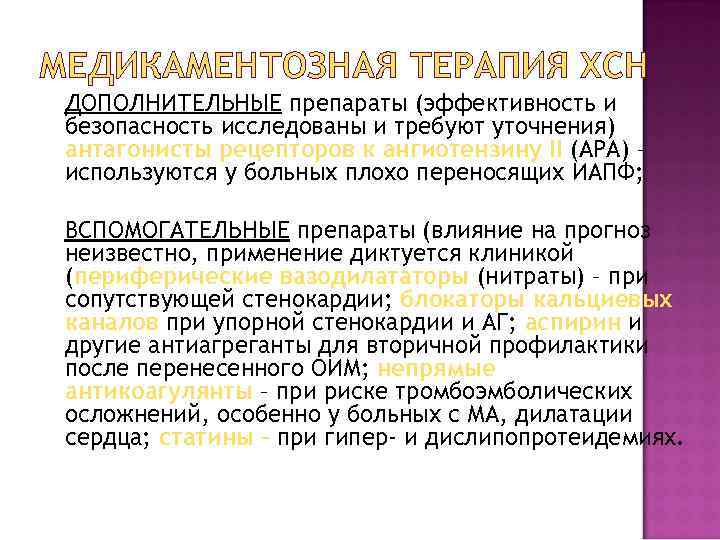

МЕДИКАМЕНТОЗНАЯ ТЕРАПИЯ ХСН ДОПОЛНИТЕЛЬНЫЕ препараты (эффективность и безопасность исследованы и требуют уточнения) антагонисты рецепторов к ангиотензину II (АРА) – используются у больных плохо переносящих ИАПФ; ВСПОМОГАТЕЛЬНЫЕ препараты (влияние на прогноз неизвестно, применение диктуется клиникой (периферические вазодилататоры (нитраты) – при сопутствующей стенокардии; блокаторы кальциевых каналов при упорной стенокардии и АГ; аспирин и другие антиагреганты для вторичной профилактики после перенесенного ОИМ; непрямые антикоагулянты – при риске тромбоэмболических осложнений, особенно у больных с МА, дилатации сердца; статины – при гипер- и дислипопротеидемиях.

МЕДИКАМЕНТОЗНАЯ ТЕРАПИЯ ХСН ДОПОЛНИТЕЛЬНЫЕ препараты (эффективность и безопасность исследованы и требуют уточнения) антагонисты рецепторов к ангиотензину II (АРА) – используются у больных плохо переносящих ИАПФ; ВСПОМОГАТЕЛЬНЫЕ препараты (влияние на прогноз неизвестно, применение диктуется клиникой (периферические вазодилататоры (нитраты) – при сопутствующей стенокардии; блокаторы кальциевых каналов при упорной стенокардии и АГ; аспирин и другие антиагреганты для вторичной профилактики после перенесенного ОИМ; непрямые антикоагулянты – при риске тромбоэмболических осложнений, особенно у больных с МА, дилатации сердца; статины – при гипер- и дислипопротеидемиях.